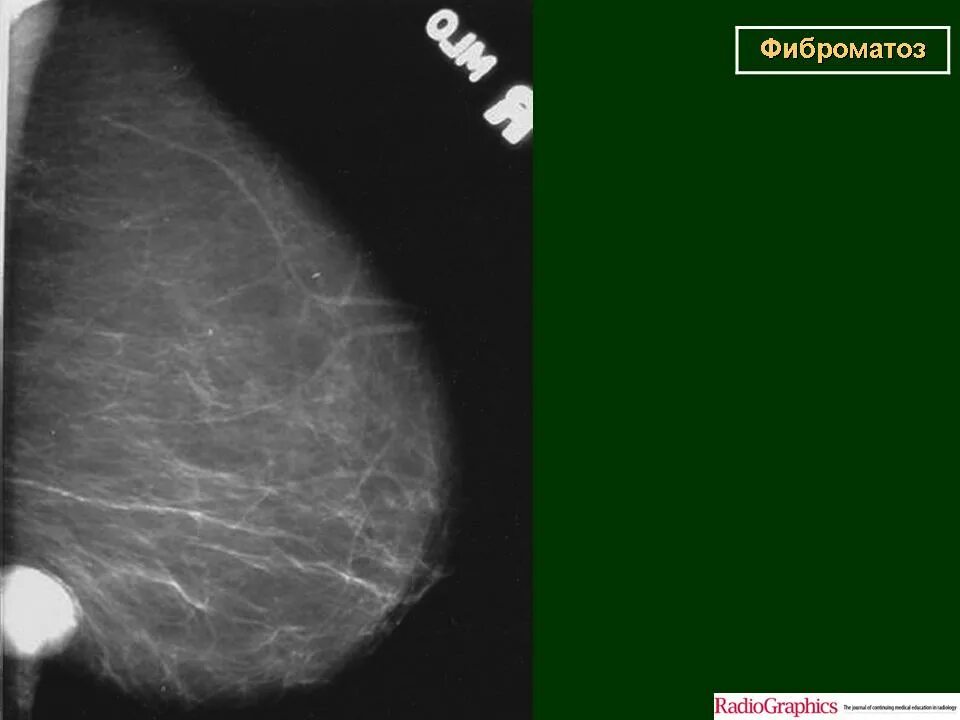

Фиброматоз мягких